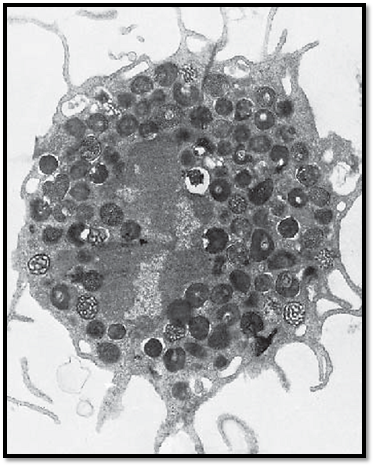

This mast cell was isolated from lung tissue. It shows long cell processes, some of which are branched. The cells establish contact with each other via these processes. This creates the image of a three-dimensional, more or less elaborate, peripheral network . In the cell center is an arcuate, notched nucleus with heterochromatin at its periphery. The cytoplasm displays a dense, finely granular matrix. Apart from this specific granulation, there are few organelles. The cell-specific, membrane-enclosed granules have diameters of about 0.5–1.5 μm. They are amorphous, both in form and structure. There are two distinct mast cell types—mucosa mast cells in the connective tissue of mucous membranes and tissue mast cells in the connective tissue of the skin.

Electron microscopy; magnification: × 13600